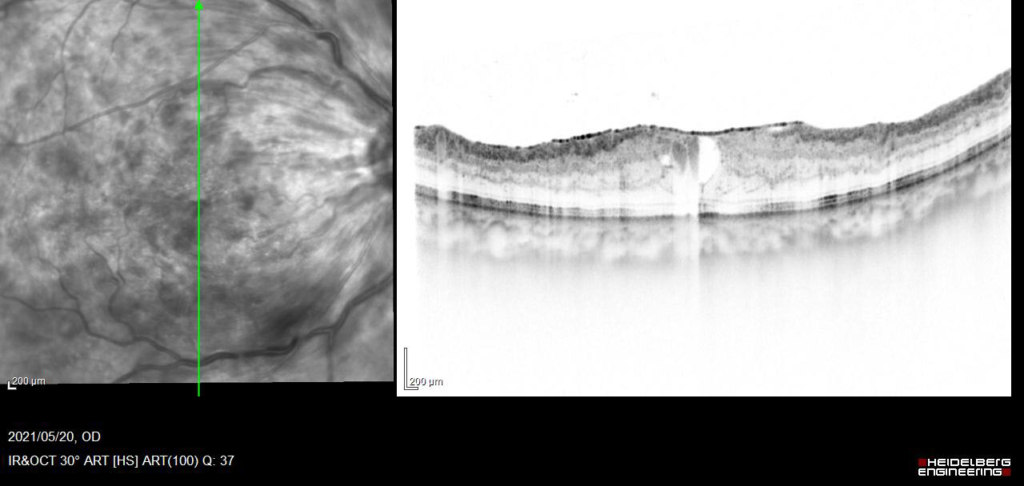

アフリベルセプトに変更し、PRP施行。

発症後約6か月後

発症後約10か月、抗VGEFの硝子体注射後5Wで黄斑浮腫のみられない状態が維持できるようになった。

現在、経過中。rubeotic glaucoma 血管新生緑内障の発症なし。

視力 右眼 0.09(n.c)